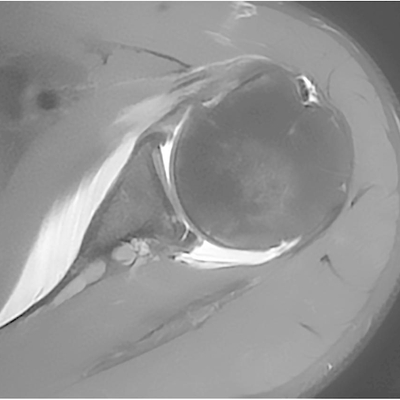

Click on an image below to view more info.